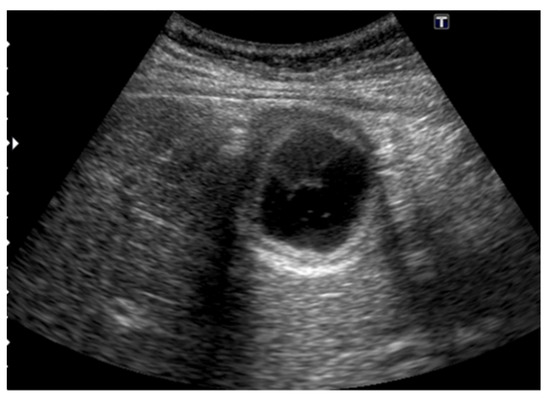

Figure 14. GBC concomitant with segmental ADM. A high-frequency transducer delineated a hypoechoic sessile GBC (arrowhead) in the fundus distal to the annular stricture (arrow).

Segmental ADM is a high-risk condition for GBC [41,70,71] (Figure 14), especially in patients older than 60 years old [70,71]. Since epithelial metaplasia was more marked in the fundal mucosa of segmental ADM than in the neck mucosa (p = 0.003) [70], GBC arose in the mucosa of the fundal compartment distal to the annular stricture of the segmental type ADM [71].